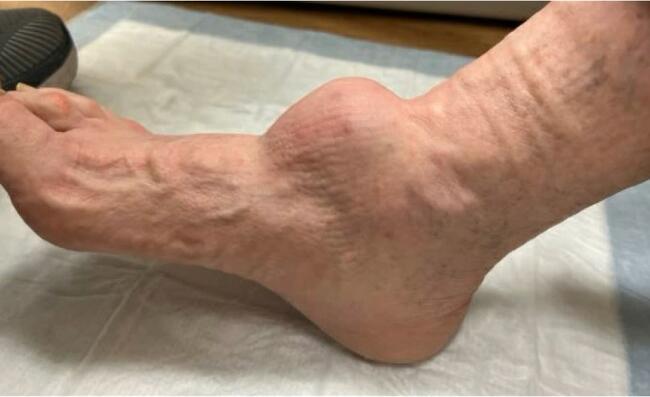

A 90-year-old male patient presented to our clinic with a chief complaint of a soft tissue mass at the right anterior ankle that had slowly increased in size over the past year. He denied pain to the lesion and denied neurological changes to the surrounding soft tissues. His past medical history was significant for lung cancer as well as basal cell carcinoma to the forearm. Physical exam revealed a 7 x 7 cm firm, well-adhered soft tissue mass protruding from the right anterior ankle (Figures 1-2).

On physical exam, he was neurovascularly intact. There was no tenderness to palpation of the mass, and ankle joint range of motion was unrestricted with full function and strength of the tibialis anterior and long extensor tendons. The patient only complained of difficulty donning shoe gear. Core biopsies of the mass, taken at an outside facility, revealed a predominantly fibrous, fibrillary hypocellular, low-grade spindle cell lesion with no signs of atypia or mitotic activity. Plain films revealed arterial calcifications but were unremarkable for any osseous erosions.